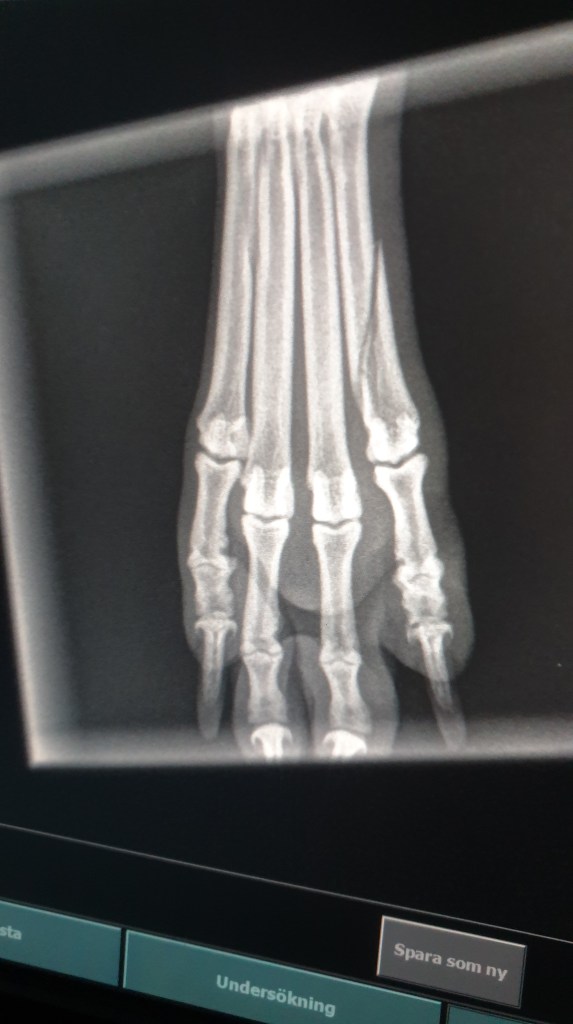

För en vecka sedan hamnade Jinnie ivägen för Vera (shettisen) och blev trampad på vänster baktass.

Vilket resulterade till ett veterinärbesök där det konstaterades att hon fått en fraktur. Så nu har hon en stödskena och äter medicin ❤